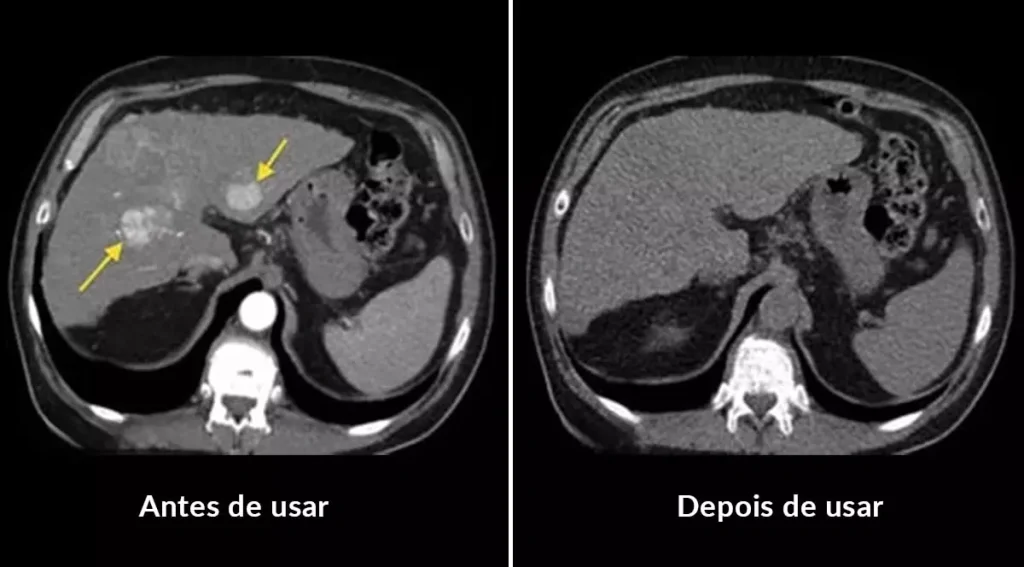

Exames da minha próstata antes e depois de usar o remédio natural Prost Force